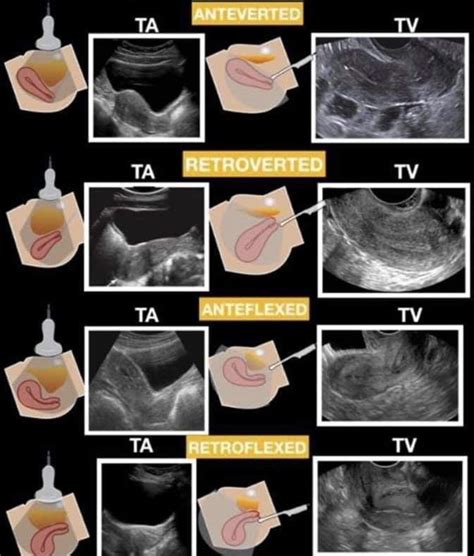

Anteverted Uterus Ultrasound

An anteverted uterus is a common anatomical variation where the organ tilts forward toward the bladder. Learn what it means when your uterus is anteverted, how this typical position affects pregnancy, fertility, and pelvic health, and discover why this natural uterine orientation is generally considered a normal finding during routine gynecological exams.